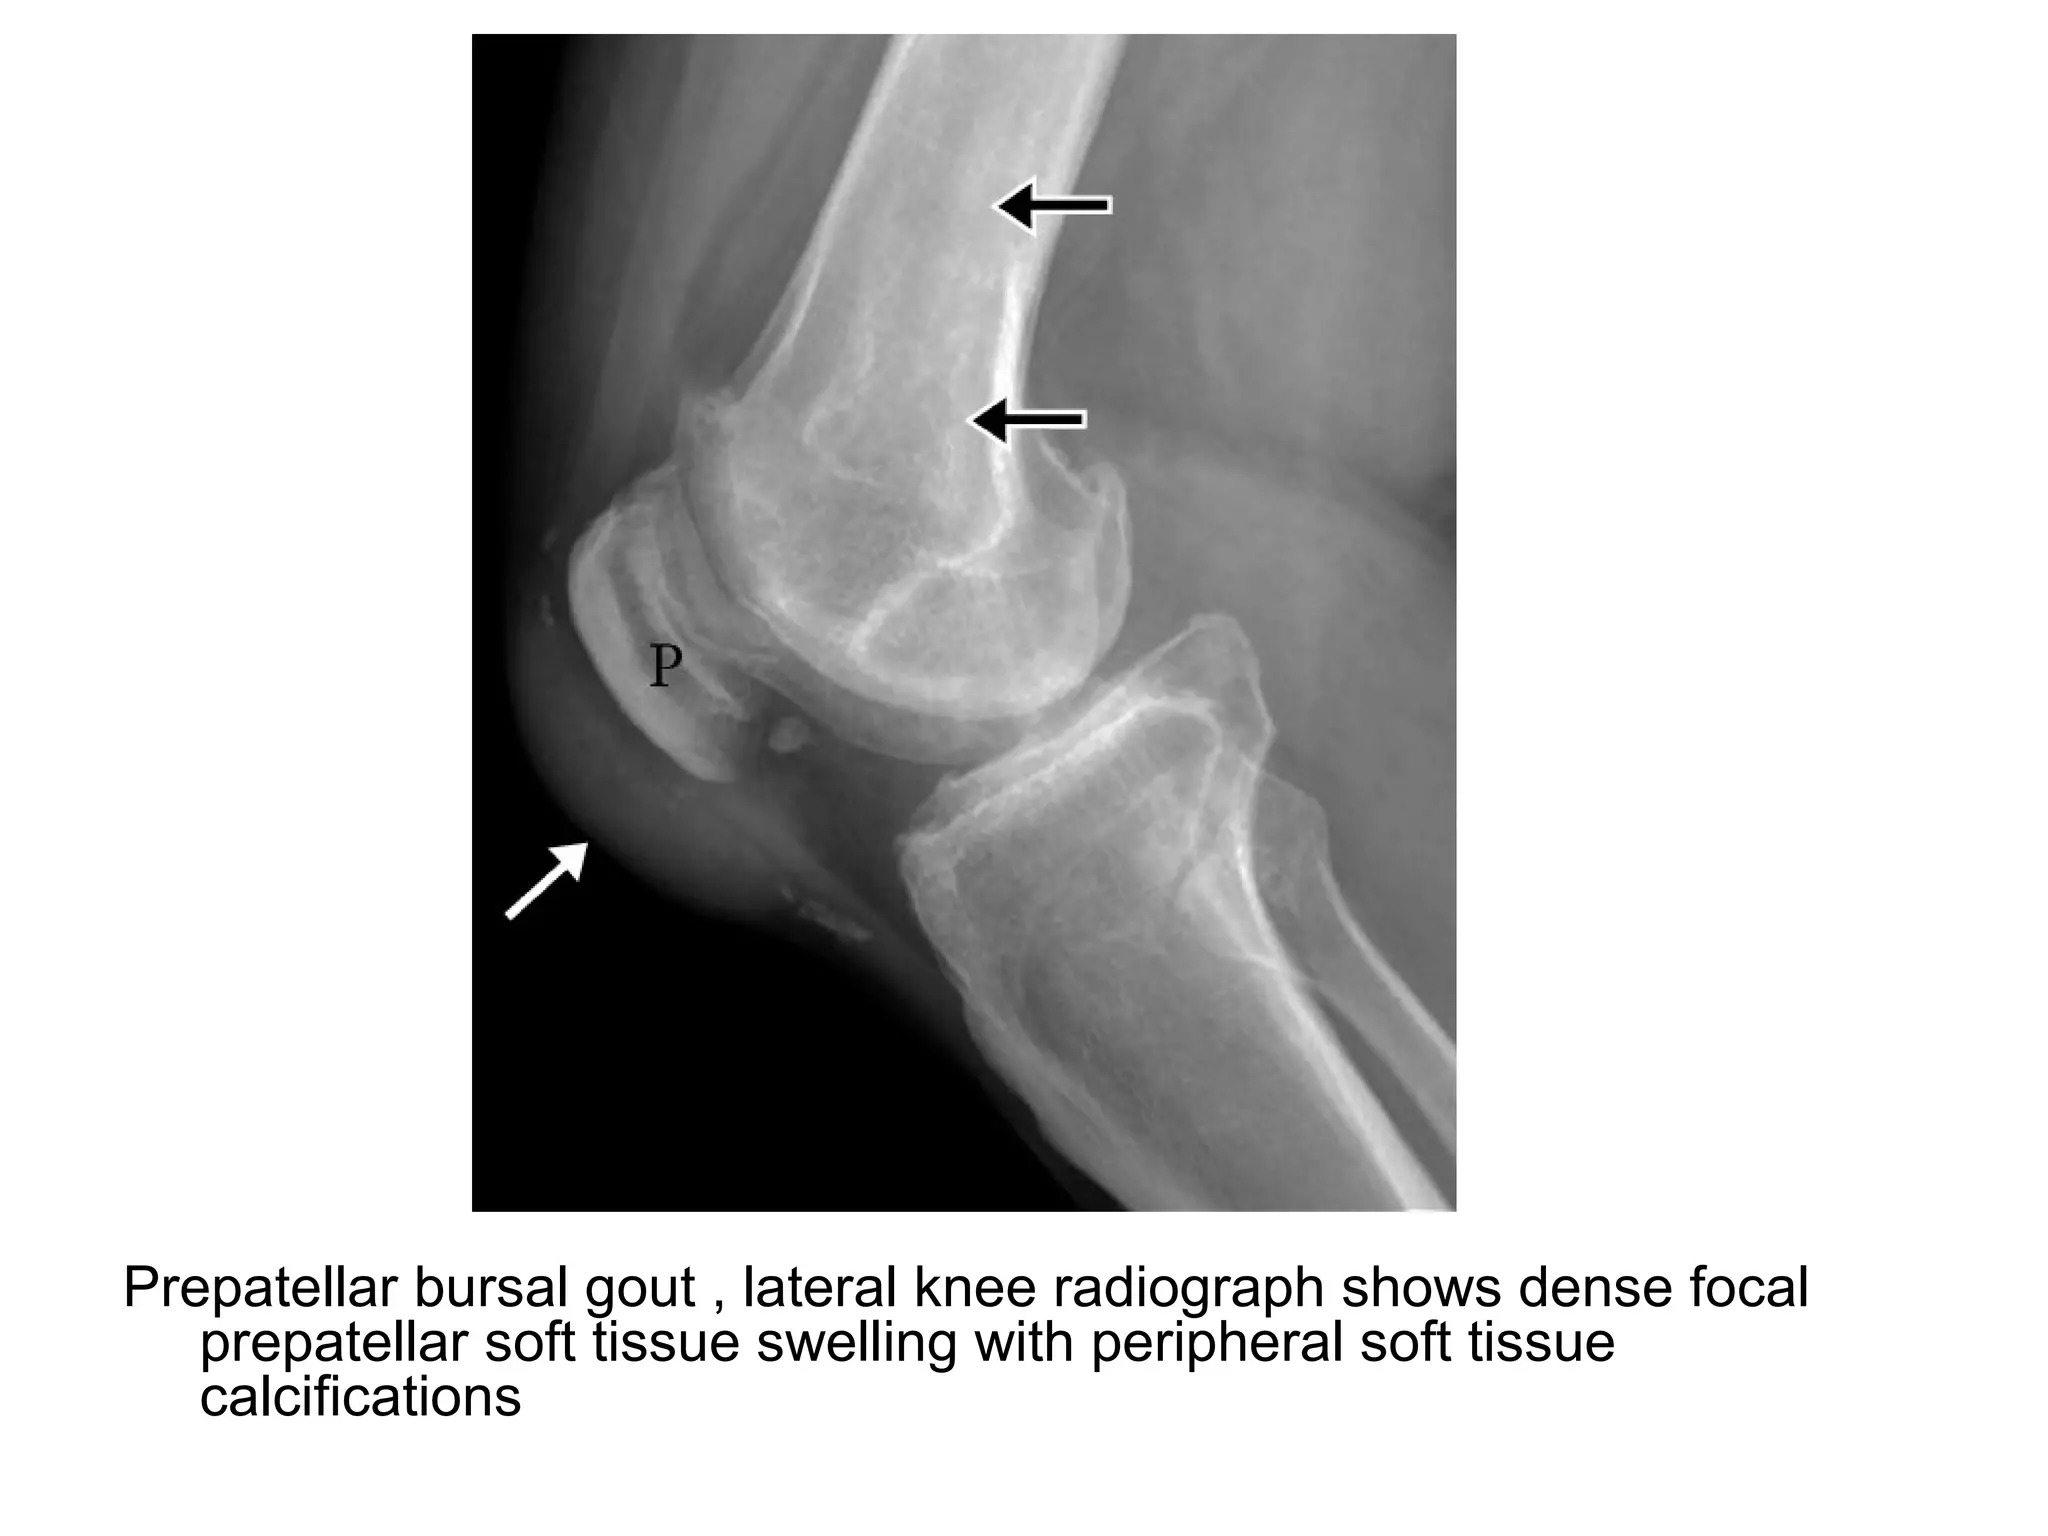

Prepatellar bursal gout , lateral knee radiograph shows dense focal

prepatellar soft tissue swelling with peripheral soft tissue

calcifications